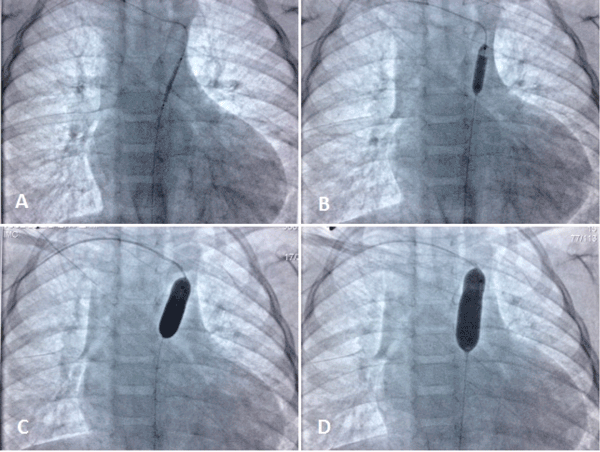

| Figure 2: A) Shows the 2 mm coronary balloon angioplasty inflated in the coarctation area. B) Shows the inflated 4 mm coronary balloon angioplasty in the coarctation. C) Shows an 8 mm balloon catheter inflated in the coarctation. D) Shows a 10 mm balloon catheter completing the dilatation of the coarctation. |